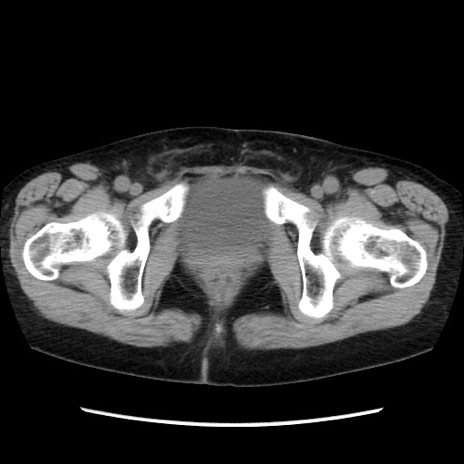

症例32(横断像)

【症例】40歳代 女性

【主訴】上腹部痛、嘔気・嘔吐

【現病歴】約9時間前頃から急に上腹部痛、嘔気、嘔吐が出現。改善しないため救急要請。

【既往歴】子宮頚癌(広汎子宮全摘術、放射線療法)、腸閉塞

【身体所見】腹部:平坦、軟、腸雑音亢進、上腹部を中心に腹部全体に圧痛あり。

【データ】WBC 8400、CRP 0.03